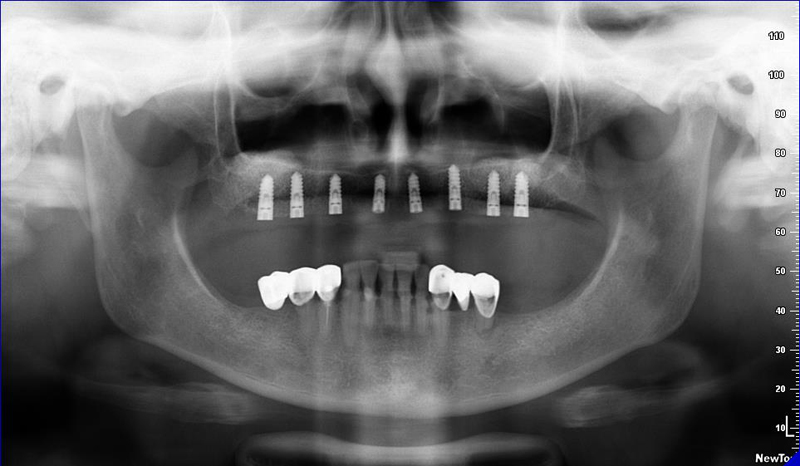

2) CB CT scan s modelem náhrady

8) Kontrolní RTG snímek po operaci

2) CB CT scan pacienta, scan modelu